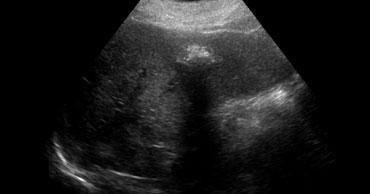

TRÁI: Hình ảnh siêu âm điển hình của u máu. PHẢI: Cũng là u máu nhưng trên nền gan tăng âm, do đó tổn thương tương đối giảm âm. Lưu ý hiện tượng tăng âm phía sau.

Siêu âm

Hầu hết các u máu được phát hiện bằng siêu âm.

Nếu phải chọn một từ để đặc trưng cho u máu trên siêu âm, từ đó có lẽ là ‘tăng âm’.

Tuy nhiên, cần nhận thức rõ rằng điều này đơn giản có nghĩa là tổn thương tăng âm so với nhu mô gan bình thường.

Nếu gan tăng âm do thoái hóa mỡ (steatosis), u máu có thể xuất hiện giảm âm (hình minh họa).

Một đặc điểm quan trọng khác của u máu là hiện tượng tăng âm phía sau.

Điều này là do tổn thương được cấu thành từ các kênh chứa máu.